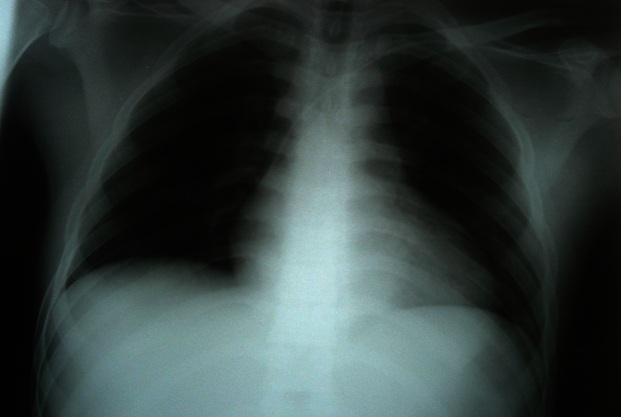

La radiographie du thorax a montré une silhouette cardiaque augmentée de taille avec une transparence pleuro-pulmonaire normale (Figure 1). L'électrocardiogramme montrait une paralysie sinusale avec un échappement jonctionnel à une fréquence de 40/min, un bloc de branche droit incomplet et des extrasystoles ventriculaires (Figure 2). L'échocardiographie transthoracique a montré une dilatation des cavités cardiaques avec un effondrement de la contractilité myocardique (hypokinésie globale avec fraction d'éjection à 20%). La tomodensitométrie cérébrale sans injection de contraste et réalisé après stabilisation hémodynamique était normale. Le bilan biologique réalisé comprenait: hémogramme, hémostase, ionogramme sanguin, urée et créatinine, glycémie, bilan hépatique (transaminases, bilirubine, phosphatases alcalines), enzymes musculaires (CPK et CPKMB), Troponine, gaz du sang et prélèvement toxicologiques. Les anomalies observées étaient une hyperleucocytose à 13000/mm3, une élévation de la créatinine sanguine à 24 mg/l et une acidose métabolique à trou anionique élevée (pH = 7.15 et HCO3 = 12 meq/l et trou anionique = 32 meq/l). De ce fait, le patient a fait l'objet d'une alcalinisation par bicarbonate 4.2% 500 ml en perfusion dans l'objectif d'améliorer l'efficacité de l'adrénaline administrée. Le patient est décédé après 12 heures d'admission en réanimation par état de choc réfractaire.

Figure 1.

Radiographie du thorax chez un patient ayant présenté une intoxication massive à la cyperméthrine et à l'éthylène glycol. Elle montre la présence d'une silhouette cardiaque augmentée de taille témoignant de l'atteinte cardiaque toxique.